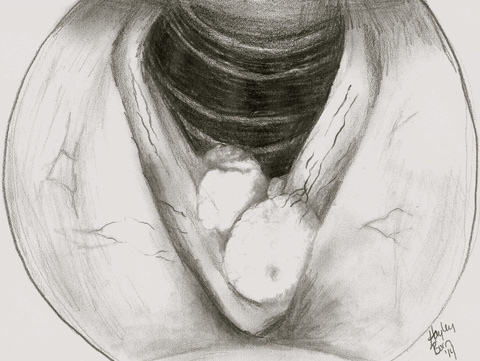

- Physical exam: flexible laryngoscopy shows verrucous, polypoid growths on the true and false vocal folds, the subglottis and/or the trachea

- Physical exam: flexible laryngoscopy shows verrucous, polypoid growths usually confined to the true and false folds, occasionally extending into the subglottic or supraglottic spaces, though rare on first presentation